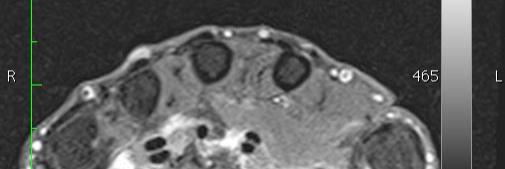

MRT Rheuma Handgelenk

Die MRT kann Rheuma an Gelenken oder Wirbelsäule frühzeitig feststellen, wenn im Röntgenbild noch keine Veränderungen bestehen (Frühdiagnostik). Nur in diesem Stadium besteht die Möglichkeit, durch eine konsequente medikamentöse Therapie das Fortschreiten einer chronischen Erkrankung aufzuhalten und in einigen Fällen die Erkrankung sogar zu heilen.